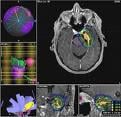

The study, Three-Staged Stereotactic Radiotherapy Without Whole Brain Irradiation for Large Metastatic Brain Tumors, aimed to evaluate the efficacy and toxicity of staged stereotactic radiotherapy with a 2-week interfraction interval for unresectable brain metastases more than 10 cm3 in volume.

Subjects included 43 patients (24 men and 19 women), ranging in age from 41 to 84 years, who had large brain metastases (> 10 cc in volume). Primary tumors were in the colon in 14 patients, lung in 12, breast in 11, and other in 6. The peripheral dose was 10 Gy in three fractions. The interval between fractions was 2 weeks.

For tumors >10 cc at baseline, staged radiation therapy with a 2-week interval between 10-Gy doses reduced tumor volume by nearly 40 percent. The researchers concluded that the 2-week interval allowed significant reduction of the treatment volume.